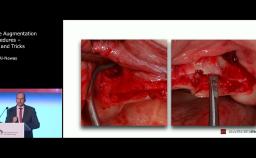

ITI World Symposium 2024 lecture by Tara Aghaloo - part of the "GBR/Bone Augmentation" session.

Many complications can be avoided by identifying and managing systemic and local risk factors before grafting is performed. As more bone grafting materials and techniques are available and being performed by a larger number of clinicians, complications must be identified and managed early and thoroughly. This lecture will highlight risk factors associated with increased postoperative complications in bone augmentation procedures, and discuss the most frequent complications associated with horizontal and vertical grafting with implant placement.